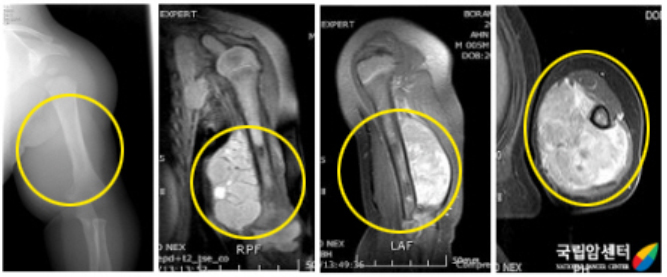

원발 병소의 자기공명영상(MRI)을 포함하여 전이의 배제를 위하여 전신검사가 필요합니다.

전이율이 높고 전이는 폐, 림프절, 골수에 흔하며, 원발병소가 사지인 경우 림프절 전이가 20% 정도로 흔합니다. 횡문근 육종은 주위 구조물에 침습을 잘하는 공격적인 종양으로 뼈에도 침습을 잘하기 때문에 외과적 절제연을 결정하기가 어렵습니다. 수술적 치료로는 광범위 절제술을 하여야 하며, 근치적 치료 후에도 재발이 되거나 조기에 폐나 림프계로 잘 전이하므로, 방사선 치료와 항암제 투여를 병행하여야 합니다.

[ 왼쪽 상완부에 횡문근육종을 가진 환아의 사진 ]

[ 위 환아의 항암약물치료 후 사진과 병리 사진 ]

방사선상으로는 관절 주위 연부조직에 원형 또는 타원형의 음영을 볼 수 있으며, 간혹 종양 내에 석회화를 나타내기도 합니다.